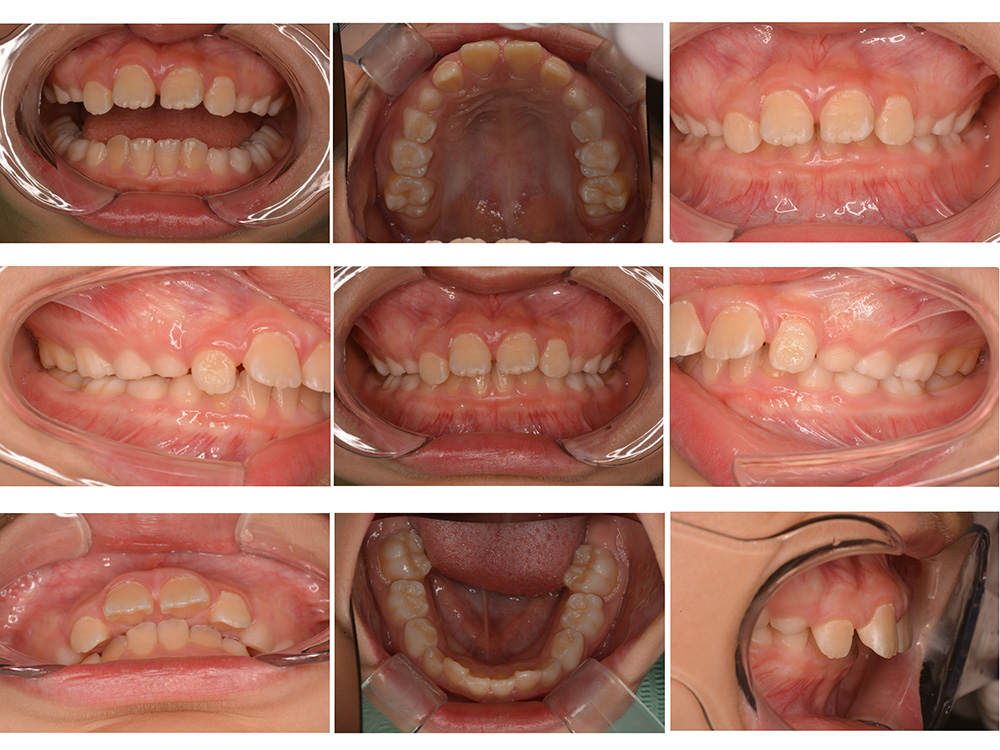

術前

術後

世代・性別

10歳女性

主訴

前歯が出ているのを治したい

治療内容

筋機能矯正治療(治療途中)

治療期間

4ヶ月

治療費

27万円(税別)

治療のリスク

歯の移動に伴う痛み